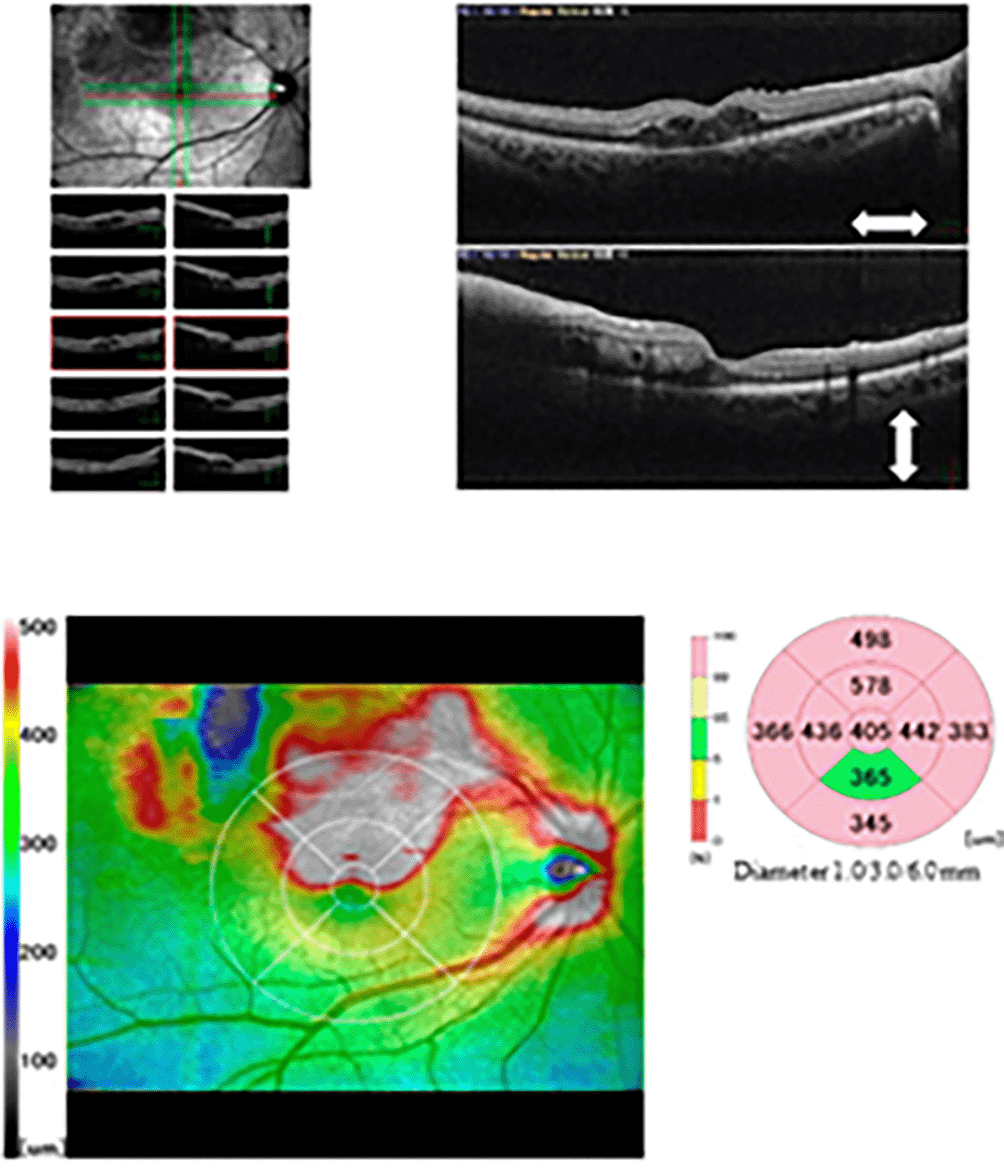

Approximately 40 days after being diagnosed with COVID-19, she presented with decreased vision in the right eye and was diagnosed with ME secondary to BRVO. On her initial visit to our hospital, the decimal best-corrected visual acuity (BCVA) values were 0.4 in the right eye and 1.2 in the left eye. In both eyes, intraocular pressure was normal, and slit-lamp biomicroscopy did not detect inflammation. Fundus examination revealed retinal hemorrhage in the superior-temporal quadrant of the retina in the right eye (Figure 1). Optical coherence tomography (RS-3000 Advance, Nidek Corporation, Japan) demonstrated cystoid ME and intraretinal fluid in the right eye (Figure 2). Blood test results, including cardiolipin antibody IgG, were within normal limits.

055ce6af-1987-409a-9553-0d8901fedf21_figure2.gif

Figure 2. Optical coherence tomography showing macular edema at the initial visit.

The clinical diagnosis was ME secondary to BRVO following COVID-19. We contacted her gynecologist about her eye condition, and oral contraceptives for oligomenorrhea were changed to a progestational hormone agent (dydrogesterone). Additionally, the patient was treated with intravitreal aflibercept (Eylea®; Regeneron, Tarrytown, NY, USA). ME resolved after 1 month (Figure 3), and the decimal BCVA improved to 1.2 in the right eye. After more than 20 months since the first administration, no additional intravitreal aflibercept has been administered.

055ce6af-1987-409a-9553-0d8901fedf21_figure3.gif

Figure 3. Optical coherence tomography showing improvement in macular edema 1 month after intravitreal aflibercept injection.